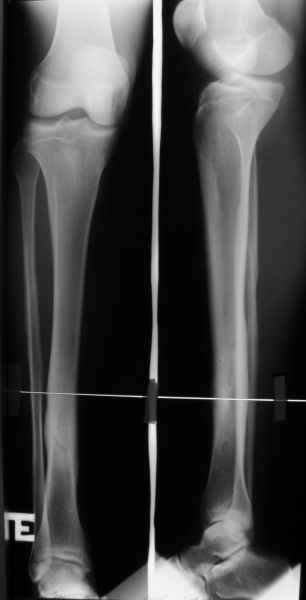

Из тона Вашего сообщения следует, что необходимо согласиться с этим,поскольку это и есть ИСТИНА. И вообще сторонники БИОСа предлагают не лезть со своими аппаратами внешней фиксации к диафизарным переломам вообще. Кстати,новым аппаратом я пролечил, ни много ни мало, уже 103 пациента. 4 дня назад я снял аппарат с 22-летнего пациента с простым косопоперечным переломом костей голени. 45 дней фиксации, из которых 30 он ходил без дополнительных средств опоры с полной нагрузкой. 3 перевязки за весь период лечения. Около 3 недель адаптационной нагрузки и его можно выписать к труду. Сегодня снял аппарат пациентке 36 лет. Фиксация 49 дней. История та же. Через два дня собираюсь снять аппарат 28-летней пациентке, 45 дней фиксации. На прошедшей неделе прооперировал 4 пациентов с переломами костей голени, во всех случаях идеальная репозиция и есть уверенность, что никто из них не донесет аппарат до 50 дней. Вопрос: чем лучше БИОС? Или я что-то недопонимаю?